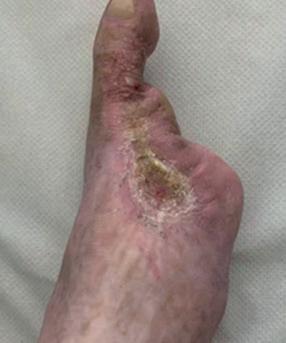

■ AOTI (Advanced Oxygen Therapy Inc)

AOTI’s TWO2 therapy is clinically proven to heal chronic wounds, reducing hospitalisations and amputations while improving quality of life and reducing costs. As an at-home therapy, TWO2 improves patient access and compliance. Our Nexa negative pressure wound therapy (NPWT) system offers simplicity, performance and affordability. aotinc.net